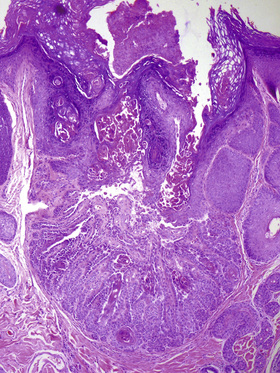

• Histology: cup-like epidermal invagination with acantholytic dyskeratosis and corp ronds/grains (Fig. 6-3)

■ “Cup-shape” and solitary nature distinguishes from Darier’s